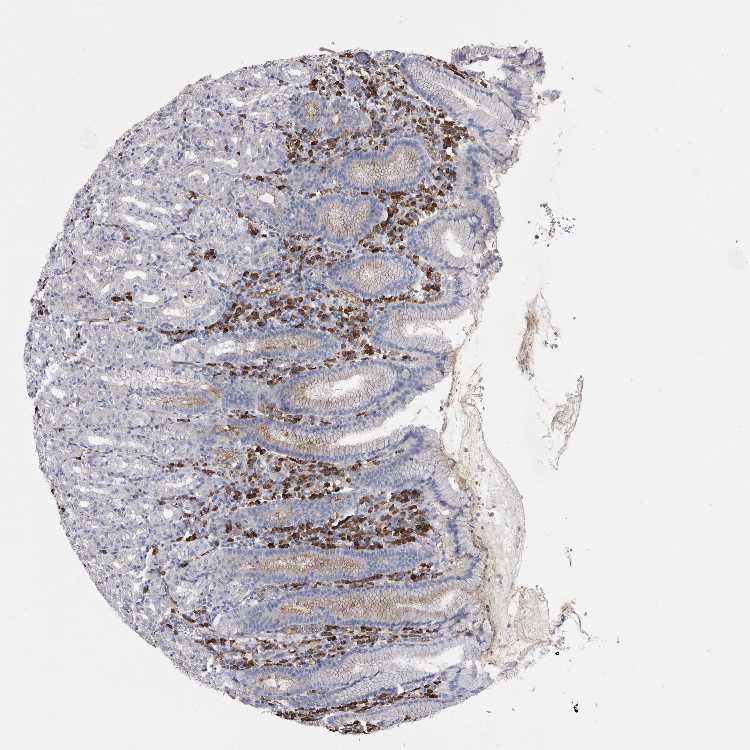

TISSUE PRIMARY DATA STOMACH Show tissue menu

STOMACH 1 - Antibody stainingi

Antibody staining in the annotated cell types in the current human tissue is reported as not detected, low, medium, or high, based on conventional immunohistochemistry profiling in selected tissues. This score is based on the combination of the staining intensity and fraction of stained cells.

Each image is clickable and will lead to virtual microscopy that enables deeper exploration of all samples and also displays staining intensity scores, fraction scores and subcellular localization as well as patient and tissue information for each sample.

Antibody HPA031355

Glandular cells Not detected

STOMACH 2 - Antibody stainingi